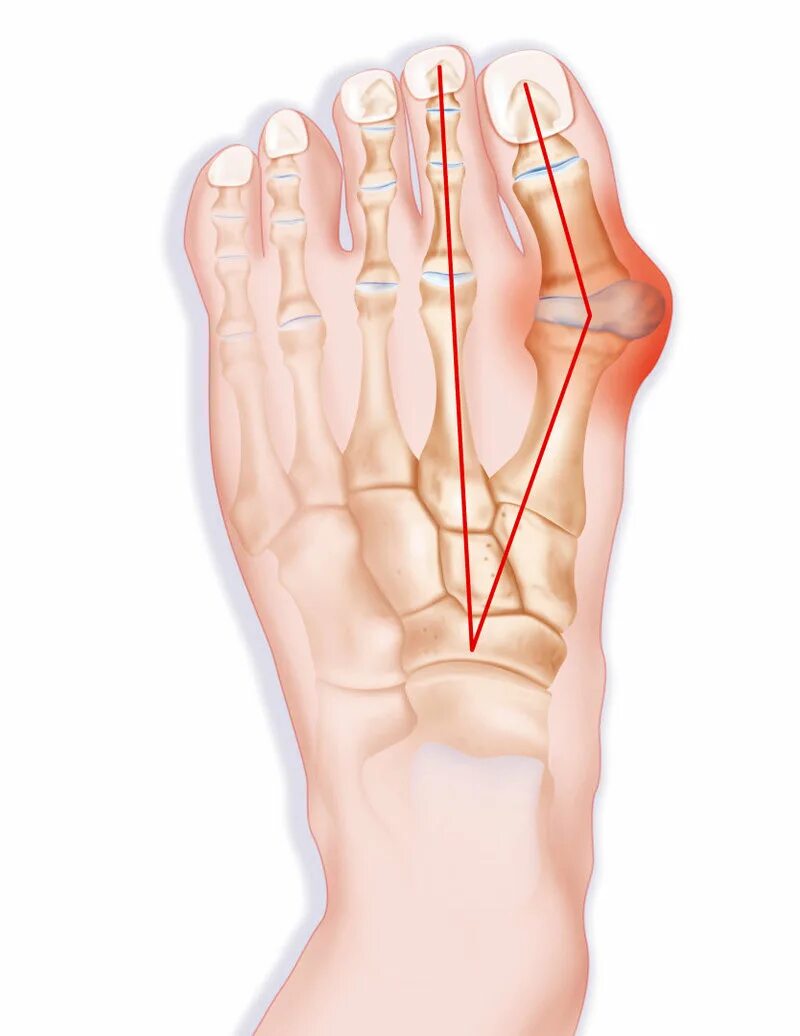

Подагра суставов стопы